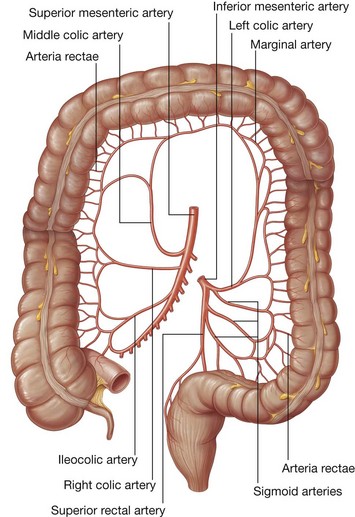

The midgut develops into the distal part of the duodenum, the jejunum, ileum, ascending colon, and proximal two-thirds of the transverse colon. A small yolk sac projects anteriorly from the developing midgut into the umbilicus.

Rapid growth of the gastrointestinal system results in a loop of the midgut herniating out of the abdominal cavity and into the umbilical cord. As the body grows in size and the connection with the yolk sac is lost, the midgut returns to the abdominal cavity. While this process is occurring, the two limbs of the midgut loop rotate counterclockwise around their combined central axis, and the part of the loop that becomes the cecum descends into the inferior right aspect of the cavity. The superior mesenteric artery, which supplies the midgut, is at the center of the axis of rotation.

The cecum remains intraperitoneal, the ascending colon fuses with the body wall becoming secondarily retroperitoneal, and the transverse colon remains suspended by its dorsal mesentery (transverse mesocolon). The greater omentum hangs over the transverse colon and the mesocolon and usually fuses with these structures.

Development of the hindgut

The distal one-third of the transverse colon, descending colon, sigmoid colon, and the superior part of rectum develop from the hindgut.

Proximal parts of the hindgut swing to the left and become the descending colon and sigmoid colon. The descending colon and its dorsal mesentery fuse to the body wall, while the sigmoid colon remains intraperitoneal. The sigmoid colon passes through the pelvic inlet and is continuous with the rectum at the level of vertebra SIII.